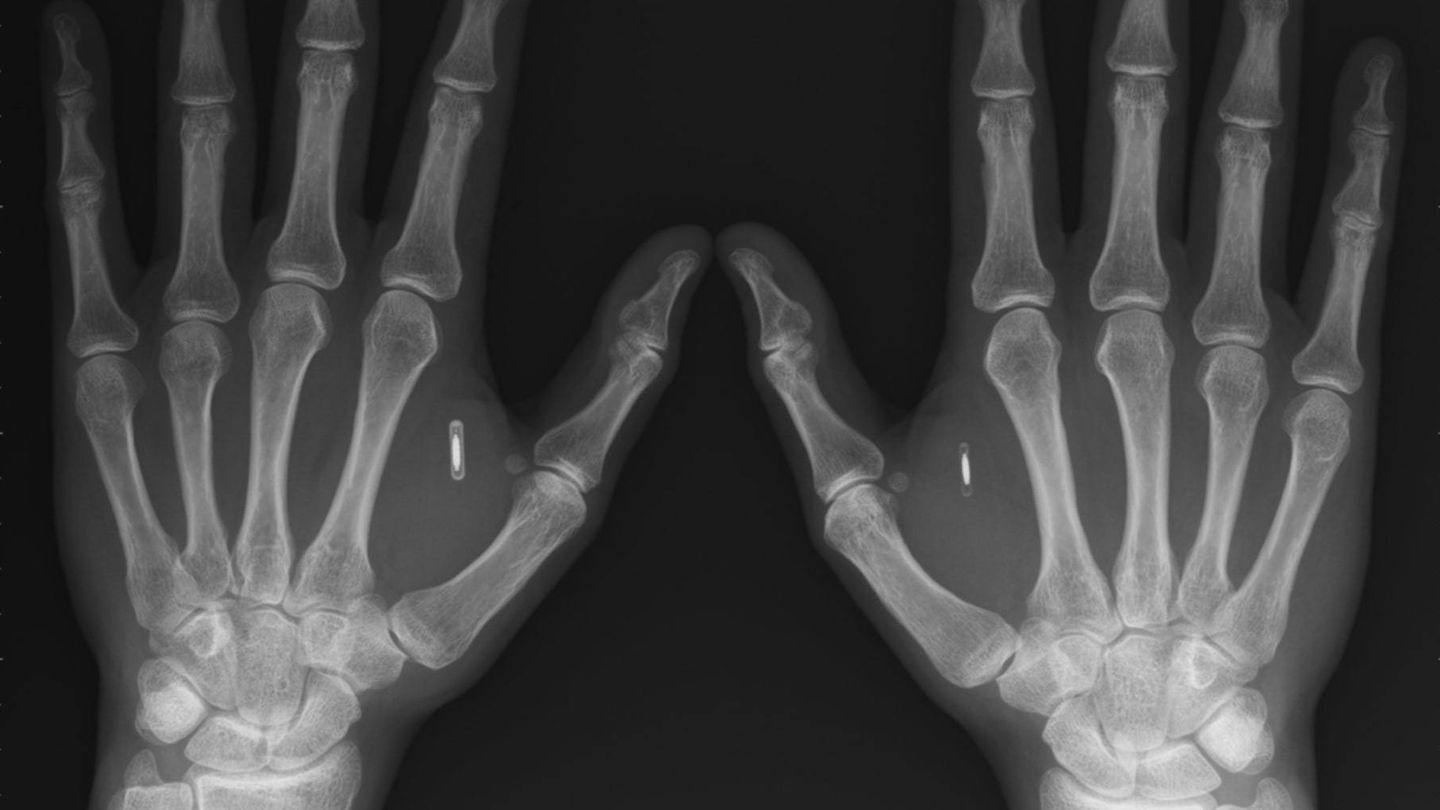

“El implante debe estar dentro del campo electromagnético de un lector RFID [o NFC] compatible. Solo cuando hay un acoplamiento magnético entre el lector y el transpondedor, el implante puede ser leído”, afirmó Patrick Paumen, quien es una de las primeras personas en colocarse un microchip. Sin embargo, uno de los principales interrogantes que surgen con su empleo, es que sucederá cuando estos comiencen ser cada vez más avanzados y se llenen de datos personales, que puedan ser robados y/o alterados.